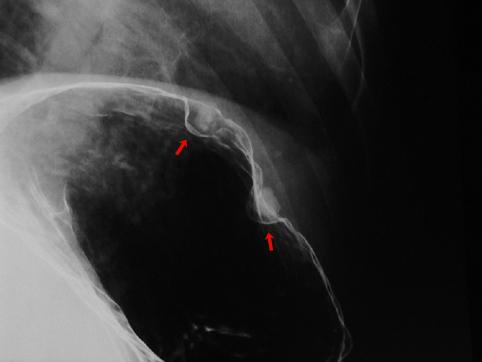

질환(병리주체)의 분류 종양양 병변/벽석탄화 병변

부위(장기별) 위(부위)/궁륭

검사방법 X-P

종양의 최대경(밀리미터) 1~9